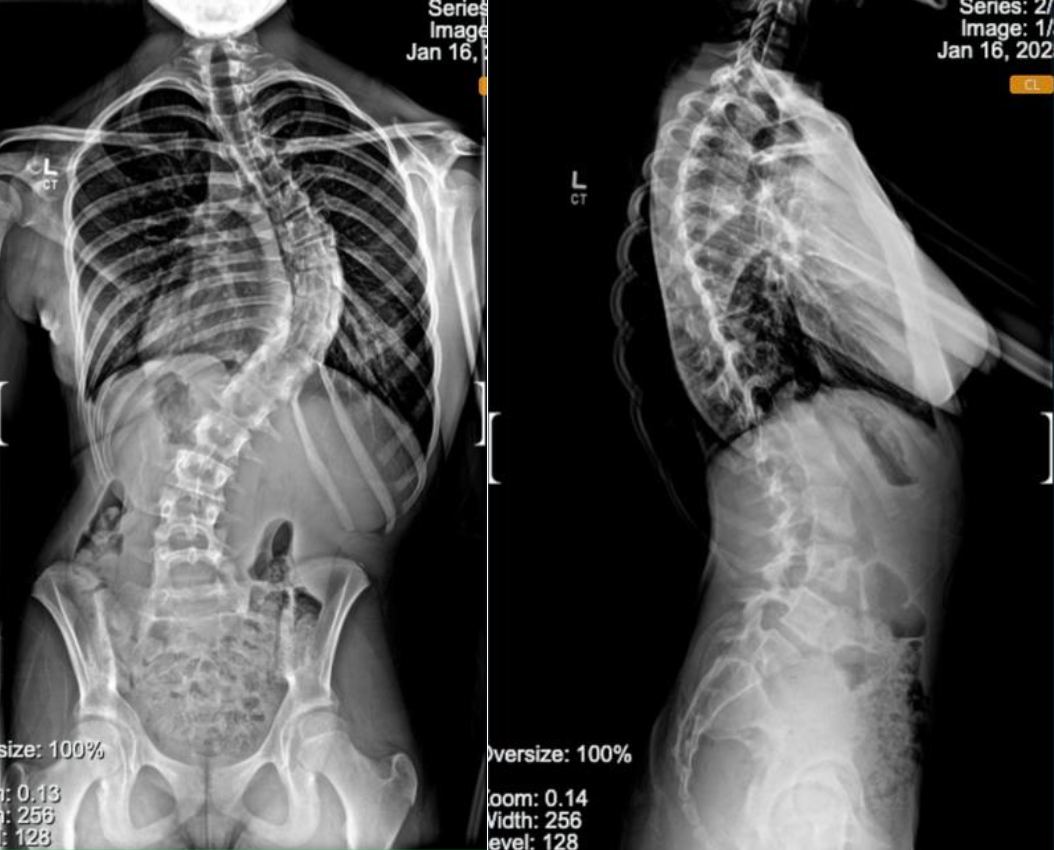

Below are before and after photos of two of our patients who underwent a posterior spinal fusion, one for scoliosis and one for kyphosis.

Scoliosis